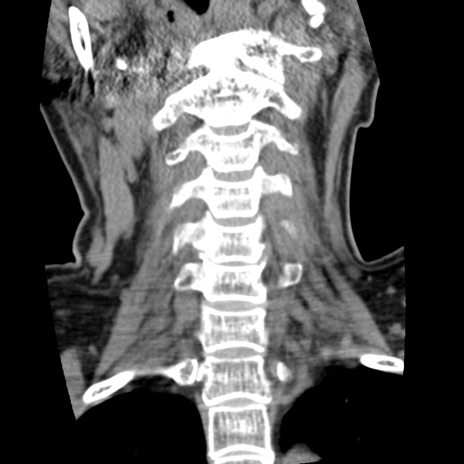

症例50 頚椎CT(冠状断像)

頚椎CT